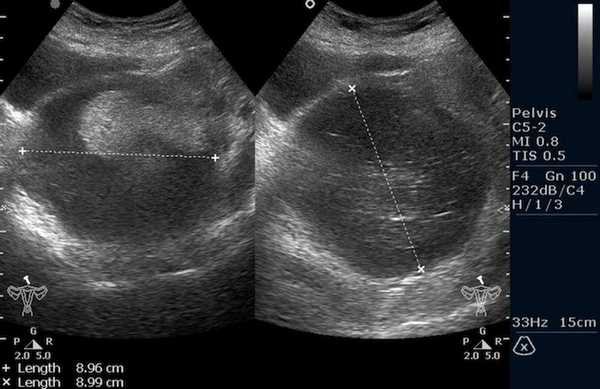

![Тератома яичника (УЗИ малого таза)]()

Тератома яичника (УЗИ малого таза)

![Тератома яичника (УЗИ)]()

![Тератома яичника (МРТ)]()

Рисунок 3. – тератома яичника а –УЗИ, б — МРТ.